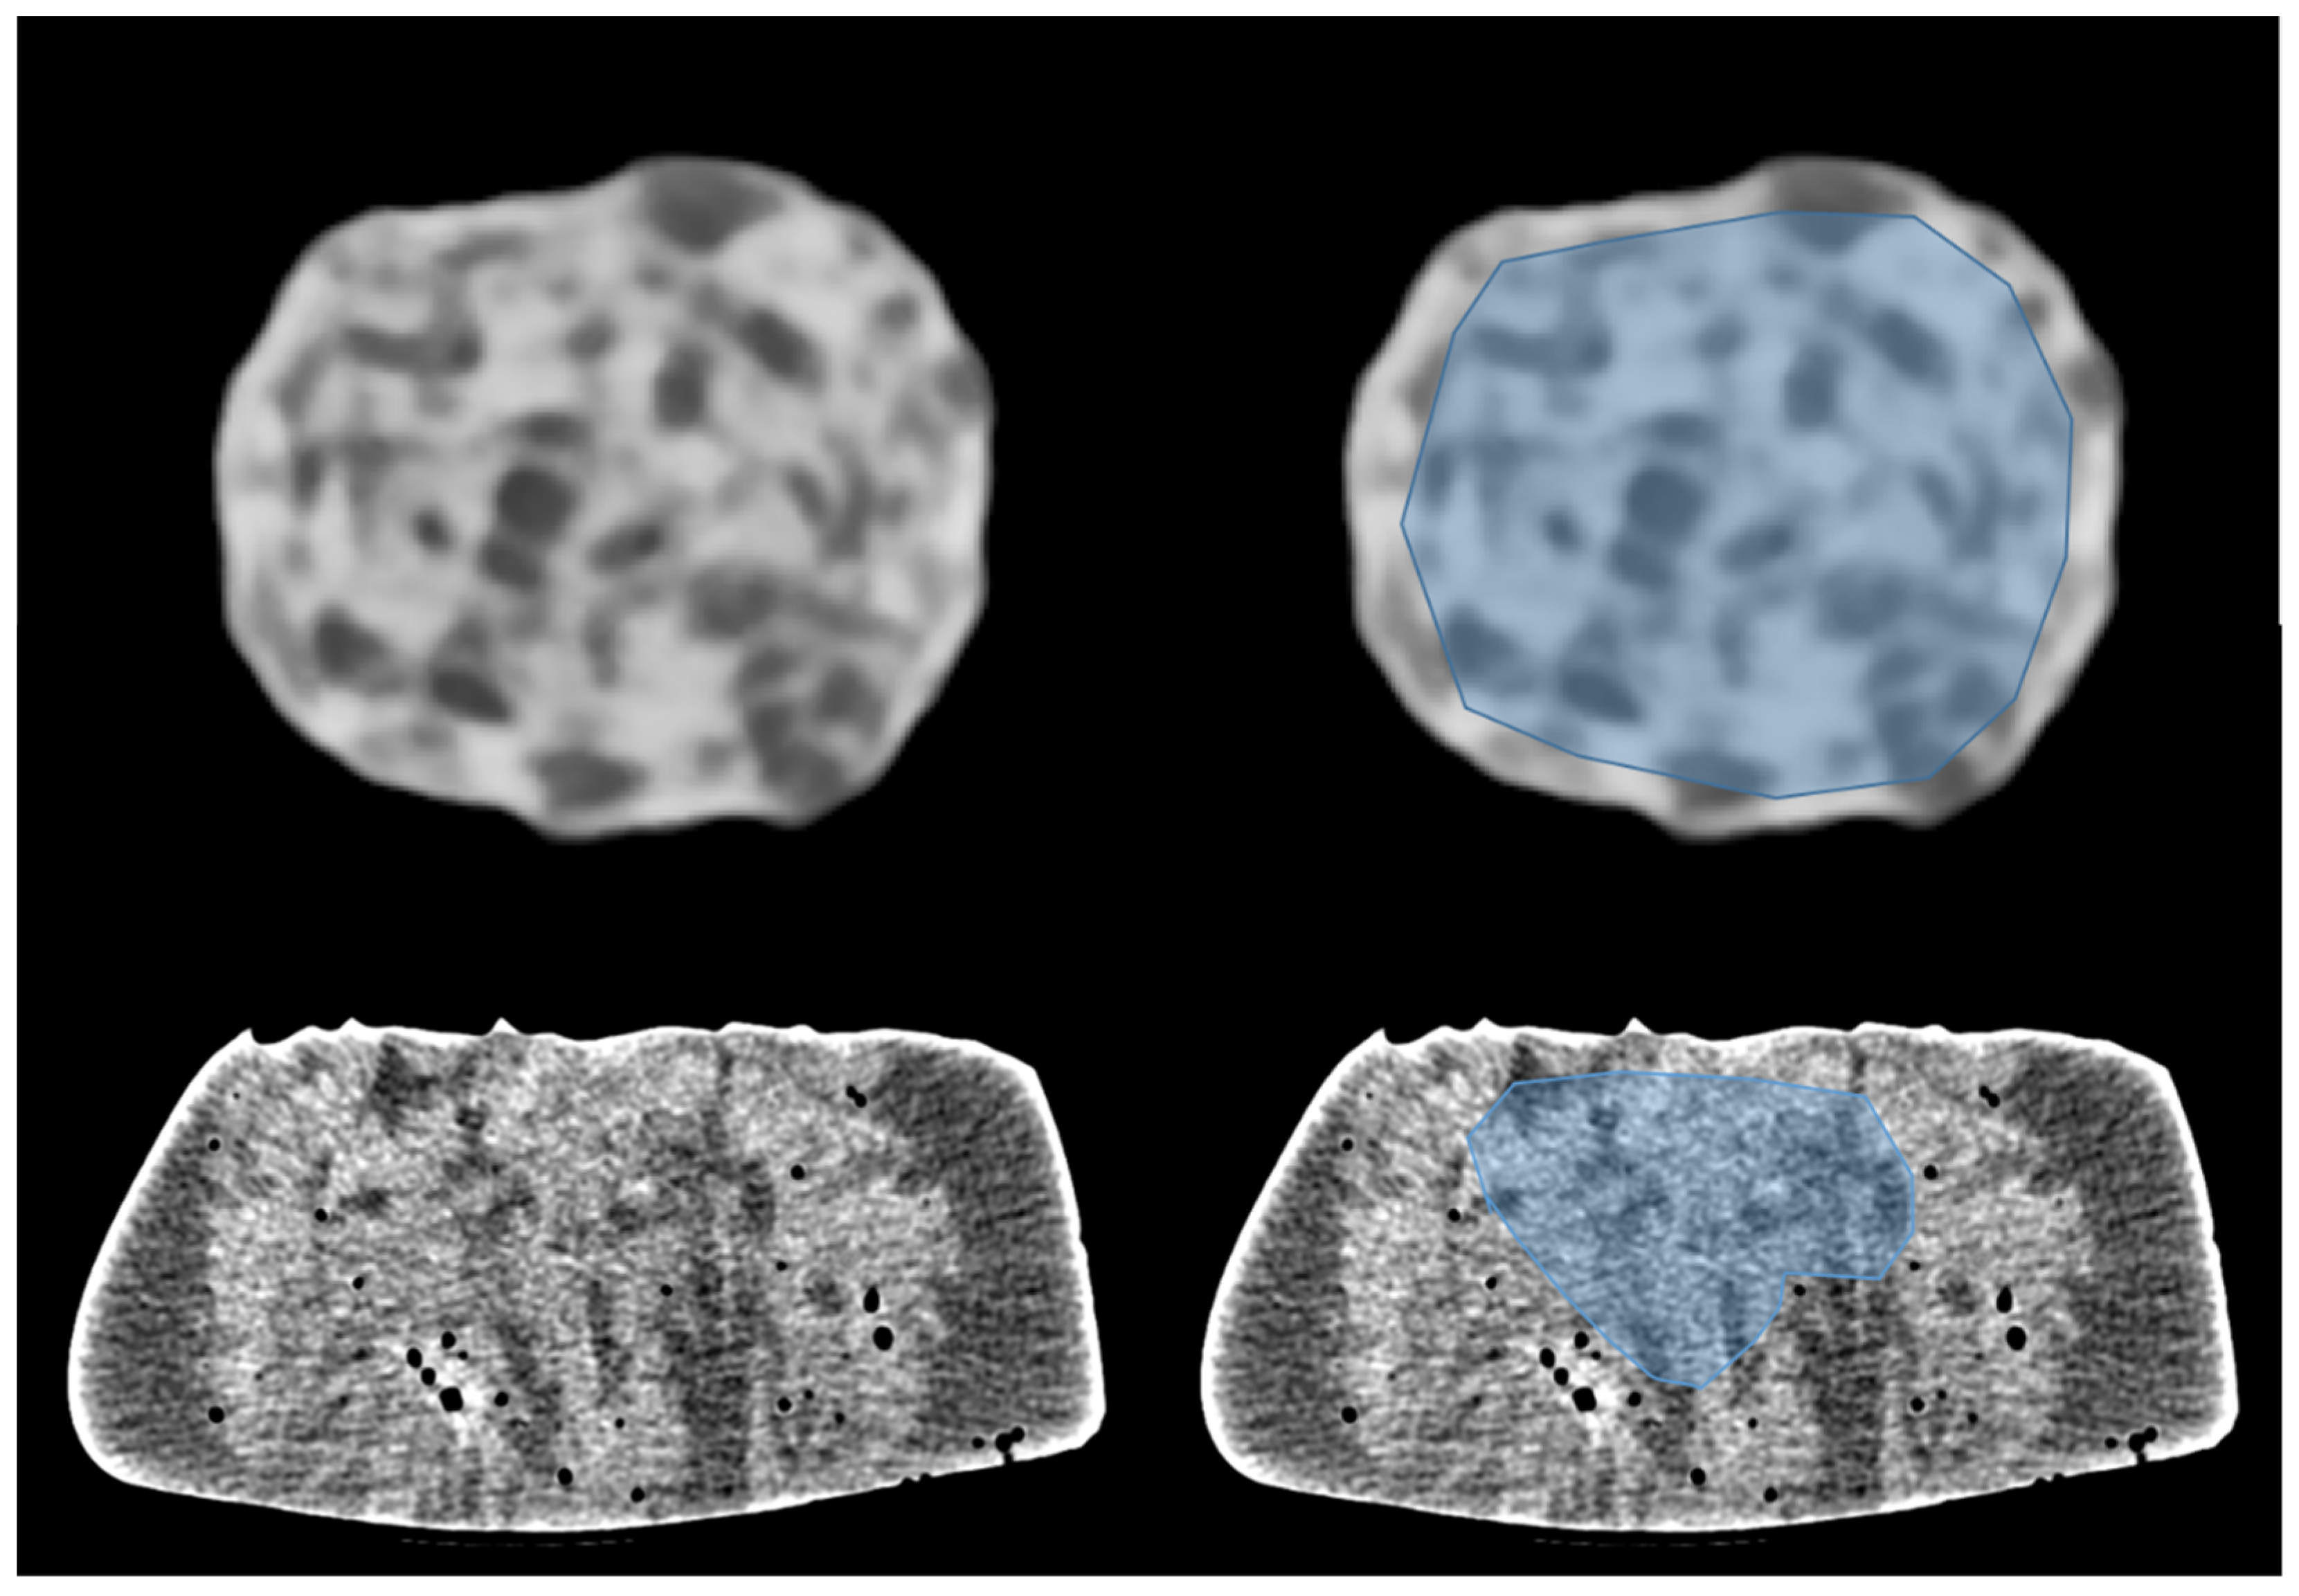

2.1. Phantom Characteristics and Imaging Parameters